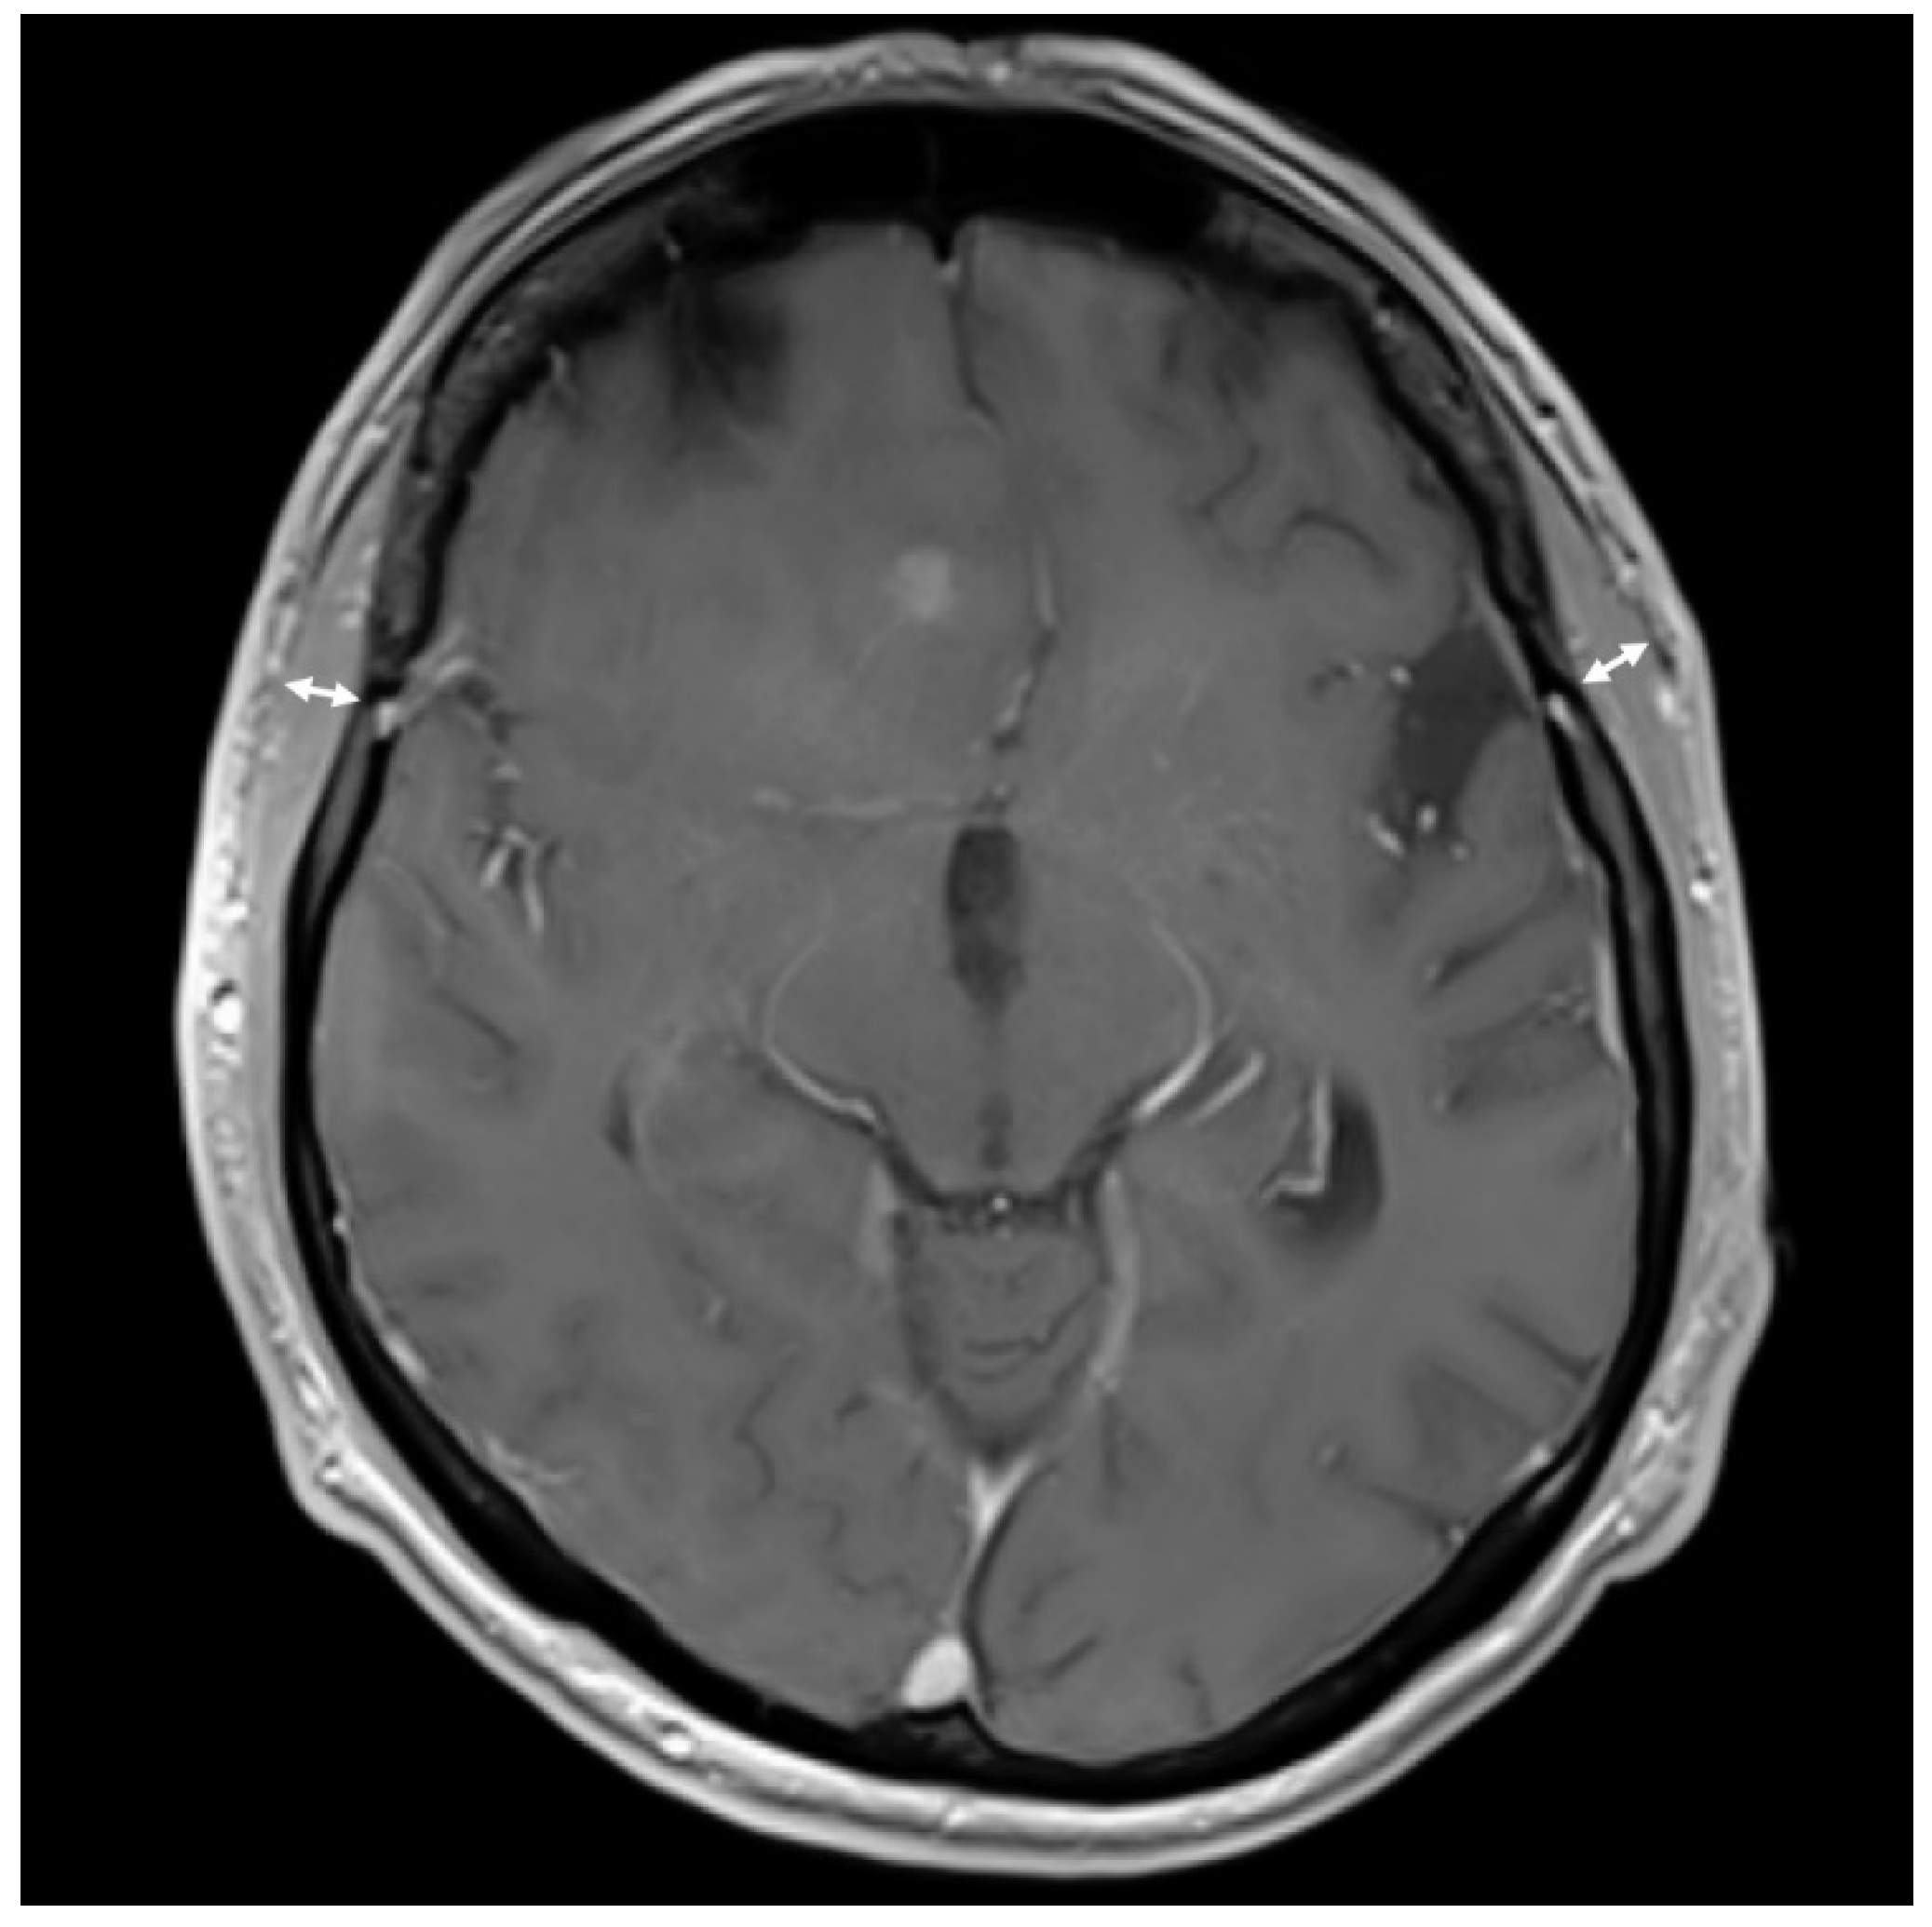

For TMT assessment, T1 weighted magnetic resonance images (MRI, 1 mm isovoxel resolution) with gadolinium in axial slides perpendicular to the axis of the temporal muscle were used. An experienced neuroradiologist who was blinded to clinical patient data measured TMT. The measurement was performed on both sides and recorded as mean TMT per patient (Figure 1).

Figure 1.

Example of temporal muscle thickness (TMT) measurement in contrast enhanced axial T1 magnetic resonance imaging (MRI) of a 70-year old male patient with an overall survival (OS) of 18 months. Measurement is marked with arrows (right: 7.6 mm, left: 7.8 mm).